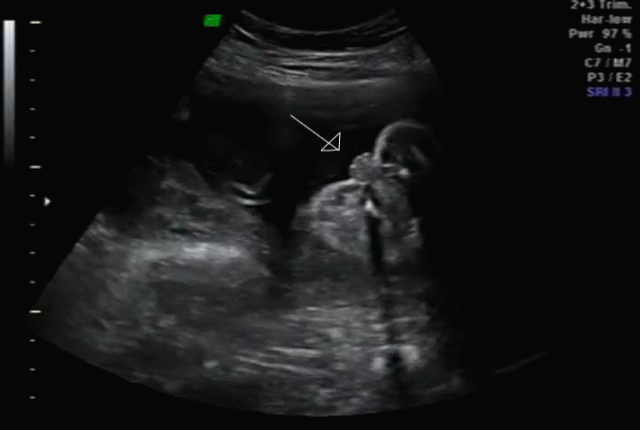

그리고 초음파 봐주시는 분께서 13주차가 되면 정확히 알 수 있으니 다음 주에 오라고 하셔서 일주일 뒤 다시 방문을 했습니다. (위에 사진은 12주 차 때 아들이라고 보여주신 초음파 사진이에요~ 화살표 보면 툭 튀어나와있는 부분을 보여주면서 아들이라고 하셨어요~)

아 진짜 전문가는 다르구나~ 이렇게 이른 주수에도 성별을 알 수가 있구나 생각을 했지만 이 시기 때는 성별을 정확히 알 수 없다는 글들을 봐서 살짝~ 의심스럽기도 했지만 그래도 100프로라니깐 ㅎㅎ 믿어보았어요~ 근데 위에 사진을 보면 성별을 알 수 있는 각도 법이 있는데 각도가 딸 같아서 긴가민가~하긴 했지만 의심은 잠시! 전문가 분을 믿기로 ㅋㅋㅋㅋ